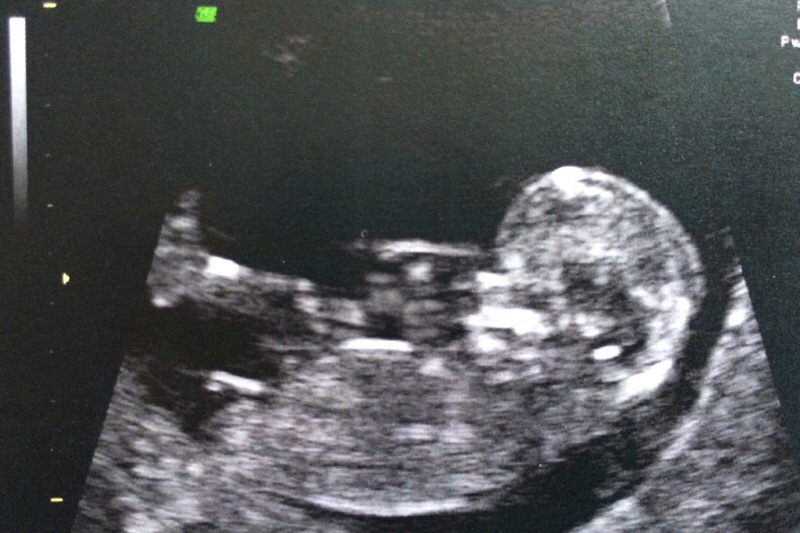

This is my 12 week scan but I am not sure if the nub is visible or how to 'guess' what it is.

Would appreciate your expert opionions. Attachment 22286